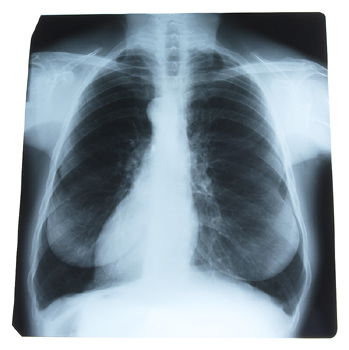

Lung cancer rates among men are on the decline

Results of the most comprehensive analysis to date of the impact of gender differences in lung cancer incidence in the United States indicate that lung cancer rates among men are on the decline, while the rate in women remains steady.Results of the most comprehensive analysis to date of the impact of gender differences in lung cancer incidence in the United States indicate that lung cancer rates among men are on the decline, while the rate in women remains steady.

A new study in the March issue of CHEST, the peer-reviewed journal of the American College of Chest Physicians, shows that, in addition to the unequal incidence of lung cancer in men and women, there are other gender-linked differences, including subtype of lung cancer and survival rate.

Researchers from the University of Michigan Medical Center and Wayne State University analyzed data of 228,572 patients (81,843 women and 146,729 men) with lung cancer who were registered in the national, population-based Surveillance, Epidemiology, and End Results (SEER) database between 1974 and 1999. Researchers found that the incidence of lung cancer in men reached a peak in 1984, when 72.5 of every 100,000 men had the disease, then declined to 47 per 100,000 men in 1991. In sharp contrast, the incidence of lung cancer in women continued to rise to a peak with 33.1 per 100,000 women in 1991, and then remained relatively stable at 30.2 to 32.3 per 100,000 women from 1992 to 1999. These variations have resulted in a male/female incidence ratio change from 3.56:1 in 1975 to 1.5:1 in 1999. For both men and women, the median age of diagnosis was 66 years. Women made up 40.9% of patients under the age of 50 but only 35.4% of patients over the age of 50.